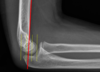

- AP and Lateral plain radiographs (see image)

- AP and Lateral radiographs (see image)

- AP and Lateral radiographs of elbow and joint below and above (see image)

- Plain film radiographs AP and lateral (see image)